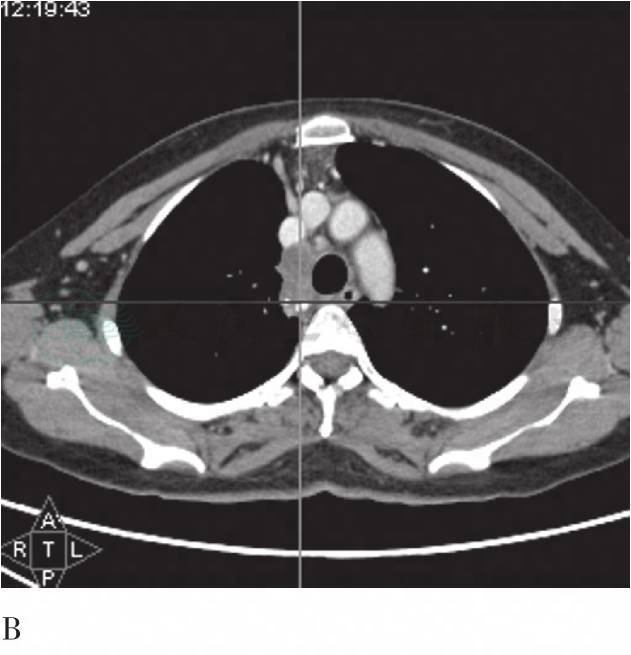

图2 FDG PET/CT胸部横断层图

A、B为第一次PET/CT(增强)图像:示纵隔4R组淋巴结肿大,增强扫描环形强化,FDG摄取增高,后部为著,SUVmax为4.6;C、D为4月后复查PET/CT(增强)图像:示纵隔镜术后,4R组未见肿大淋巴结